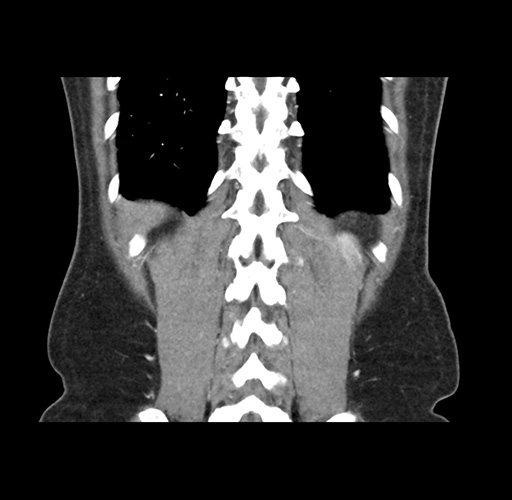

Imaging Analysis

Look through the patient's CT scan to identify any areas of concern for the necessary procedure.

Based on your CT findings, which issue(s) would give reason for "planned slowing down moment(s)" in this case?

Considering a standard left lateral sectionectomy procedure, what step(s) of the operation would you do differently in this case ?